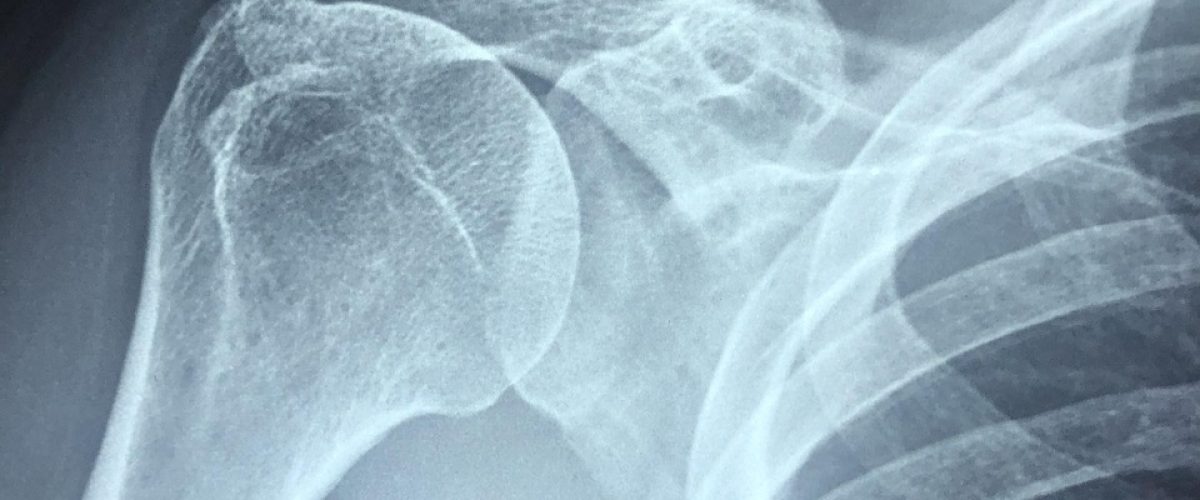

Control articular (FRC®)

Fortalecemos cada rango articular, creando control y fuerza desde dentro.